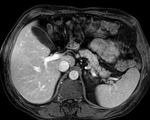

this is the intra-op CT reference image. All images are aligned into this space lleft this is the pre-op MRI we seek to align with the intra-op CT

fixed image/target moving image

unregistered MRI & CT

after linear (affine) registration

after nonrigid registration

comparing kidney alignment at different registration stages